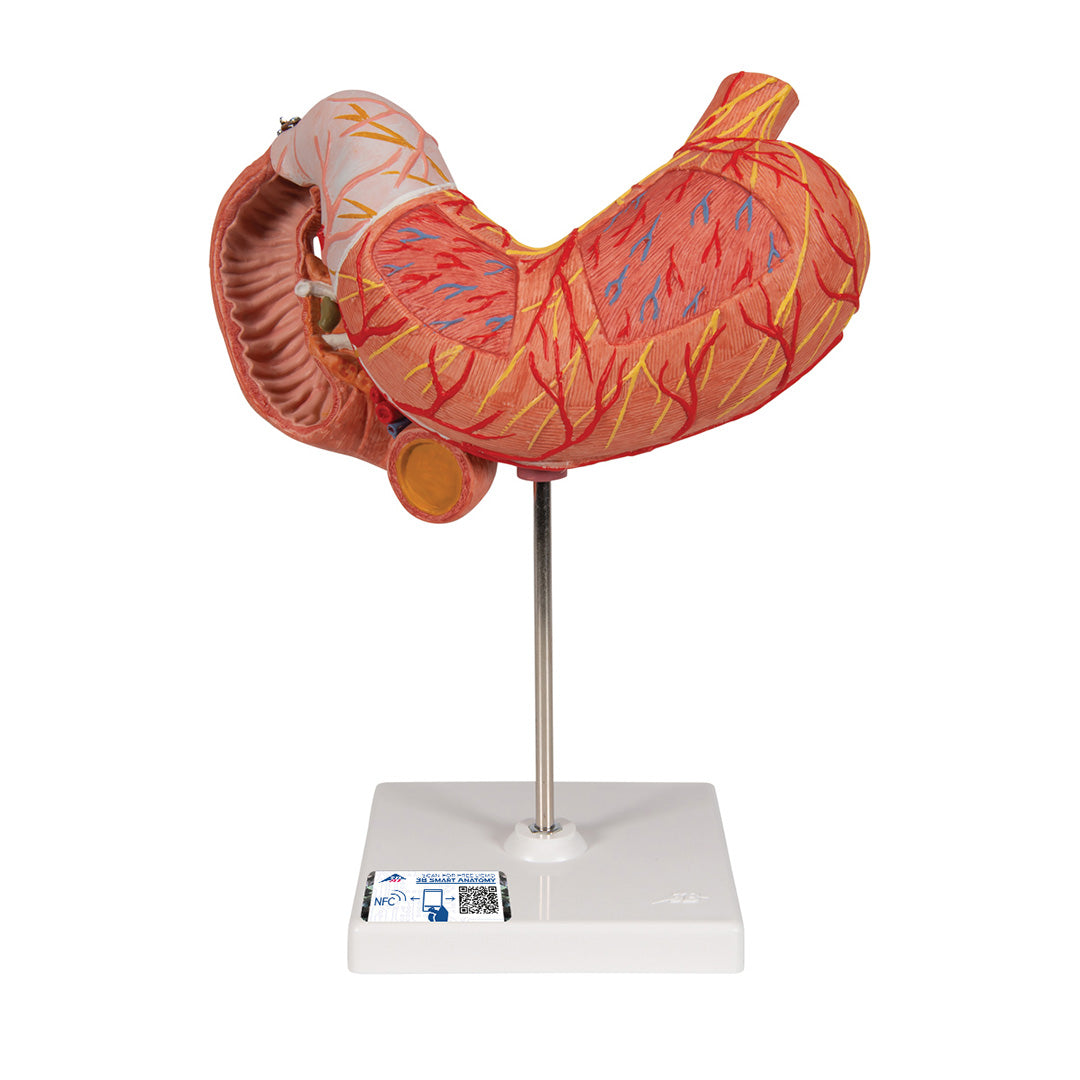

Estómago, en 3 piezas

Estómago, en 3 piezas

El modelo presenta las capas de la pared del estómago desde la cardia hasta el píloro.

La mitad delantera del estómago se puede retirar.

Se presentan:

• Parte inferior del esófago

• Conductos

• Nervios

• Duodeno

• Páncreas

Con soporte.

Peso 0.87 kg.

Dimension 25 x 22 x 12 cm